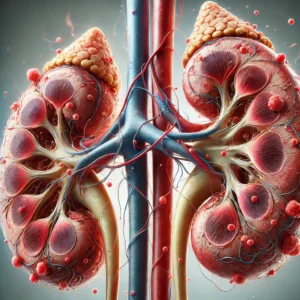

Os rins são órgãos extremamente complexos e desempenham diversas funções vitais no organismo. Muitas pessoas acreditam que a principal função dos rins é apenas “filtrar o sangue”, mas isso é apenas uma parte do que eles fazem. Os rins também regulam o equilíbrio de líquidos, controlam os níveis de eletrólitos como sódio e potássio, participam do controle da pressão arterial e produzem hormônios importantes, como a eritropoetina, responsável pela produção de glóbulos vermelhos.

Além disso, os rins atuam no metabolismo da vitamina D, contribuindo para a saúde óssea, e ajudam a manter o equilíbrio ácido-base do organismo. Ou seja, são órgãos que trabalham 24 horas por dia, de forma contínua e altamente precisa.

Quando ocorre falência renal, todas essas funções são comprometidas, e é justamente aí que entra a diálise como uma forma de suporte — mas não como uma substituição completa.